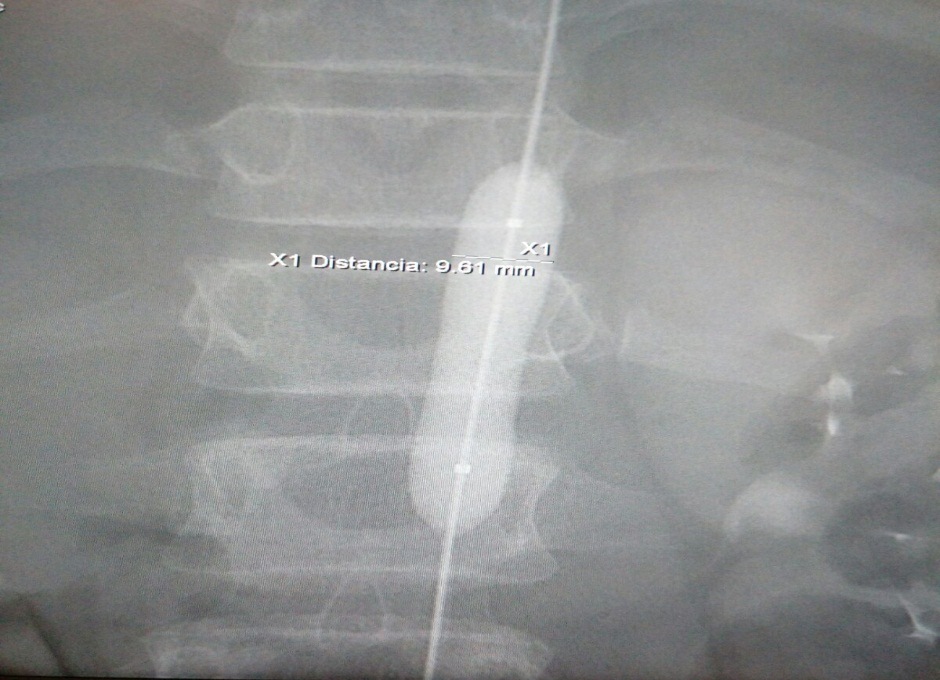

DIAGNÓSTICO FINAL: sindrome de aorta media

El síndrome de aorta media (SAM) consiste en una estenosis de la aorta abdominal generalmente con inclusión de las arterias renales y viscerales. Es un síndrome poco frecuente, aunque se considera una causa importante de hipertensión arterial (HTA) en niños y adolescentes. Se cree que su origen embriológico se debe a un fallo en la fusión de las dos aortas dorsales y la etiología es idiopática en un alto porcentaje. Su localización es interrenal en el 54% de los casos. Clínicamente cursa con HTA, sintomática o no. A la exploración puede apreciarse soplo abdominal, pulsos femorales disminuidos o ausentes y diferencia de TA entre miembros superiores e inferiores. El diagnóstico definitivo se alcanza por arteriografía y angio-RM, principalmente (2).

La aproximación terapéutica incluye el manejo médico inicial (tratamiento antihipertensivo), continuando con técnicas invasivas como angioplastia y/o intervención quirúrgica (prótesis, injertos u otras técnicas). El tratamiento médico conservador es factible hasta que el control médico de la hipertensión sea insatisfactorio, la función renal esté en riesgo o haya síntomas de claudicación de miembros o isquemia intestinal (2).